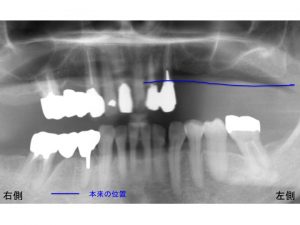

上顎左側奥歯が欠損しています。

4歯分の欠損です。

そのため、左側では噛めない状態となっています。

この欠損の手前の歯(2歯)ですが、

これらは神経がない歯です。

先にも書きましたように神経のない歯は、非常に脆く折れることが高頻度で起こります。

今回の患者様も神経のない歯が折れている状態でした。

抜歯が必要になります。

まず現在の骨の位置です。

骨が吸収することで問題が起こります。

赤線です。

次に青線です。

これは元の状態の骨の位置です。

骨が吸収する前です。